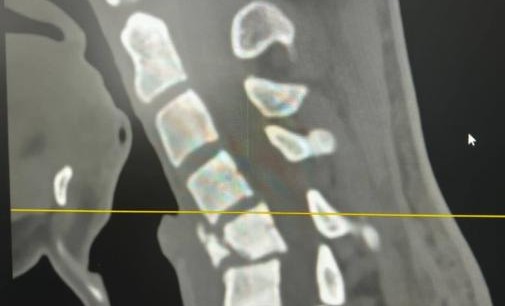

В Республиканскую клиническую больницу им. Ш.Ш. Эпендиева экстренно был доставлен пациент, который после неудачного падения на спину стал ощущать сильную слабость во всём теле и боль в шейном отделе позвоночника. У больного также наблюдалась неврологическая симптоматика: онемение в руках и ногах с нарушением двигательных возможностей конечностей. После проведенного КТ-исследования выявили выраженный перелом 5 позвонка шейного отдела позвоночника с миграцией отломков и деформацией шейного отдела.

Операция по проведению корпоэктомии шейного отдела позвоночника прошла удачно: деформация устранена, а сломанный позвонок заменен протезом. Пациент чувствует себя хорошо и быстро идет на поправку, сообщил министр.